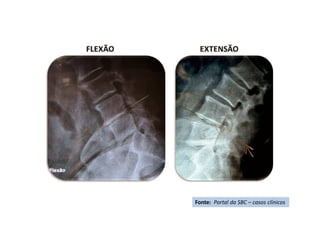

Rx ortostático AP - Pré-

operatório

Fonte: Portal da SBC – casos clínicos

Radiografia

Ortostática de Perfil –

Pré operatória

Inclinação lateral

direita

Inclinação

lateral

esquerda